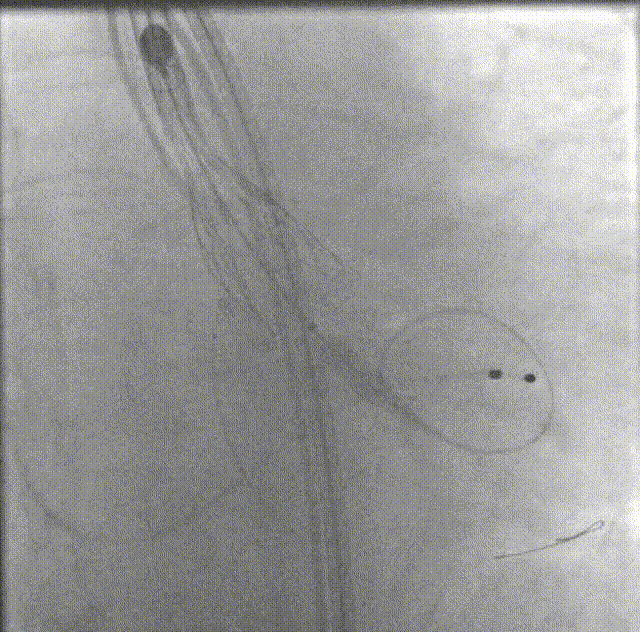

• 以右侧股动脉为主入路;

• 选用18mm球囊进行预扩;

• 植入VitaFlow®TAV24瓣膜。

术中操作

18mm球囊预扩

支架预埋

瓣膜首次定位释放

瓣膜释放至2/3

回收瓣膜再释放

多体位下观察植入深度

释放完成